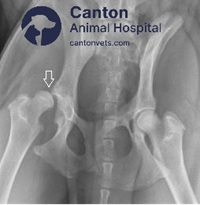

Hip Joint Subluxations in Dogs

Hip dislocation in dogs can result from trauma or joint disease. Learn the signs, treatment methods, and how to prevent future injuries.

Hip Dysplasia in Dogs

Hip dysplasia is a common joint condition in dogs that can lead to discomfort and mobility issues. At Canton Animal Hospital in Michigan, we offer expert diagnosis and advanced treatment options to help your pet stay active and pain-free.